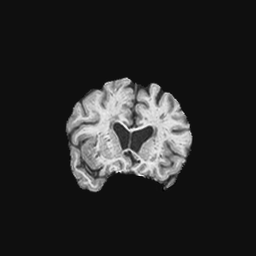

Exp. 1: Segmented adult brain data is used to evaluate our network’s regression performance with known ground truth Tisubscript𝑇𝑖T_{i}. 85 brains from the ADNI data set[1] were randomly selected; 70 brains for ΩtrainsubscriptΩ𝑡𝑟𝑎𝑖𝑛\Omega_{train} and 15 brains for ΩvalidationsubscriptΩ𝑣𝑎𝑙𝑖𝑑𝑎𝑡𝑖𝑜𝑛\Omega_{validation}. Fig. 2 shows an example slice of the ground truth and the reconstructed ΩΩ\Omega.

Figure 2: Example slice from the segmented adult brain MRI data set (a); reconstruction from 300 ωisubscript𝜔𝑖\omega_{i} based on SVRNet regression without SVR (b); SVR initialised with SVRNet predictions after eight iterations of SVR (c). Note that SVRNet (b) predicts individual slice transformations only from image intensities without any initial world co-ordinates of the sampled slice. (d) shows the achieved PSNR in dB when comparing the volumes of (b) and (c) to (a).

Reconstructing from Ti^^subscript𝑇𝑖\hat{T_{i}} initialisation without SVR yields a PSNR of 23.7 ±plus-or-minus\pm 1.09; with subsequent SVR the PSNR increases to 29.5±plus-or-minus\pm2.43 when tested on 15 randomly selected test volumes after four iterations of SVR.